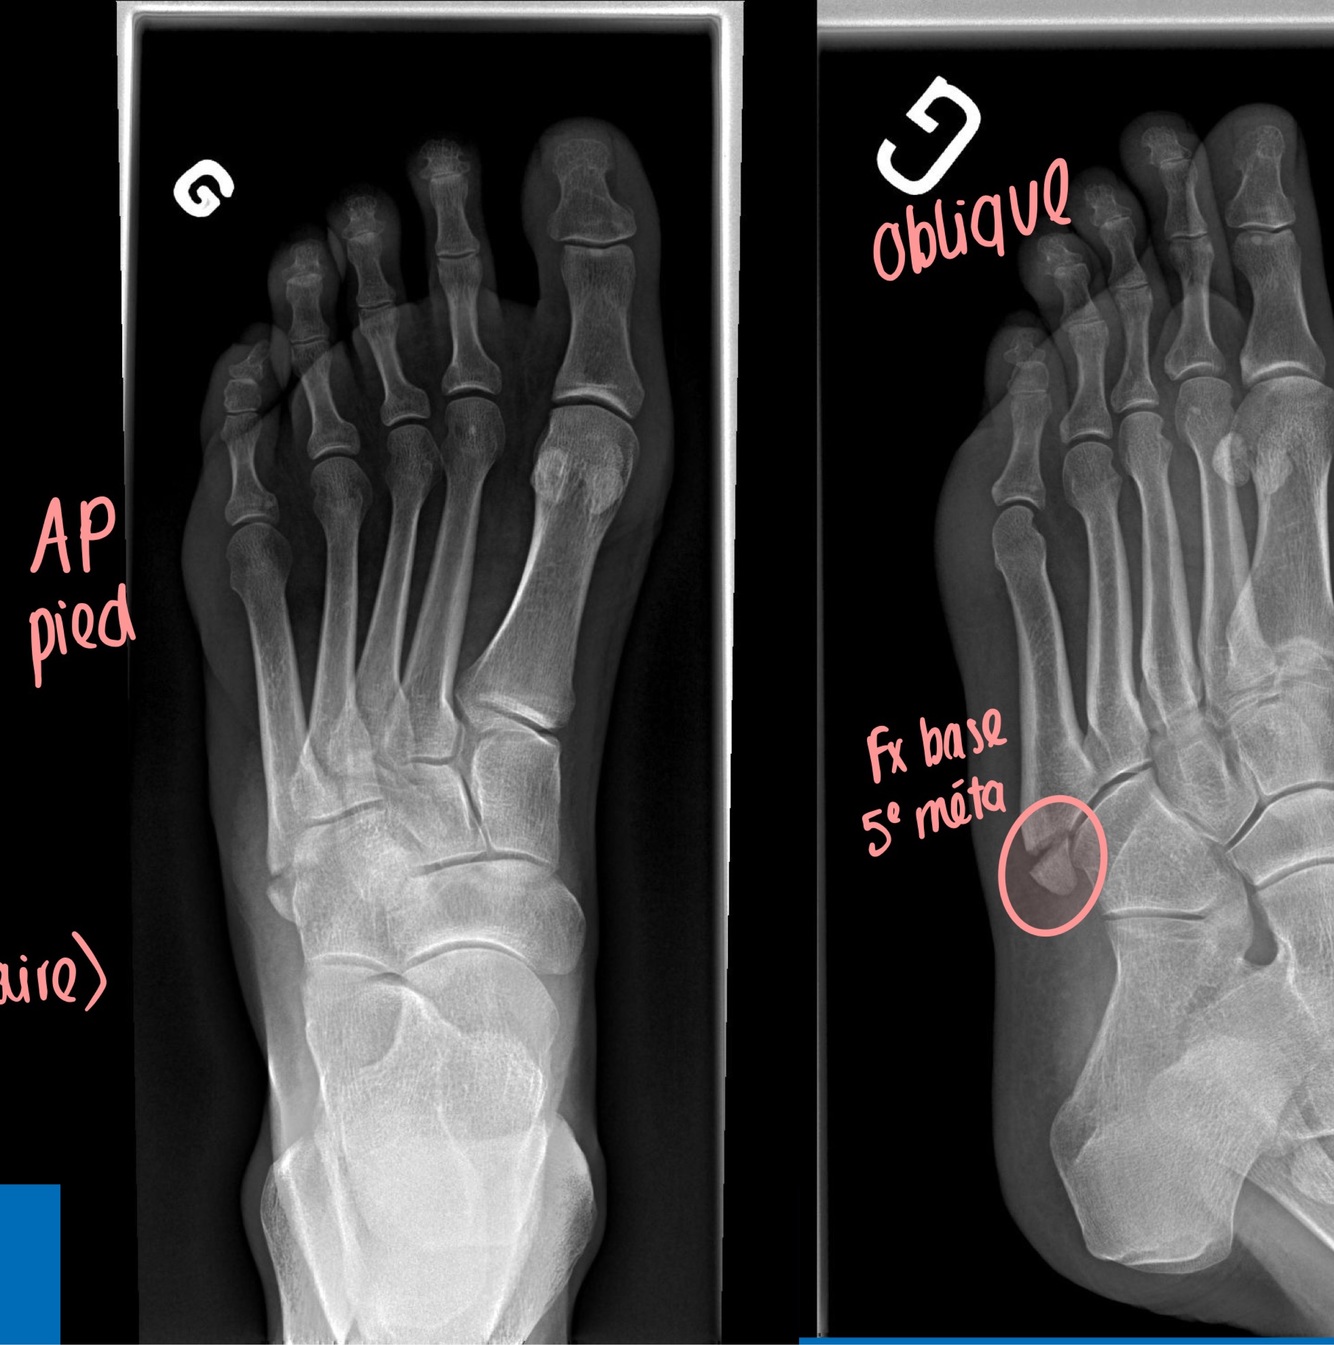

Q

Quelle vue?

Évalue quoi ?

A

Projection oblique

Évaluation de:

• Utile pour les luxations et subluxation médio-

tarsiennes, pour enlever certaines surimpositions (ex les os sésamoïdes) et visualiser la base du 5ième métatarsien

• Le bord interne du 3ième méta est aligné avec le bord interne du 3ième cunéiforme

• Le bord interne du 4ième méta est aligné avec le bord interne du cuboïde

• Doit toujours être demandée post trauma (critère Ottawa +)

7

Dx?

Et vue?

Entorse en éversion avec avulsion (court fibulaire)